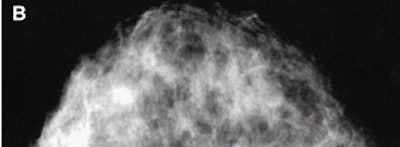

| Scintimammogram of the left breast (C) showed focal area of radiotracer uptake in upper (arrow) outer (arrowhead) quadrant. |